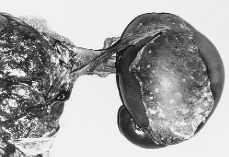

Se le realiza a la paciente un test de Clements que resulta intermedio y una amniocentesis evacuadora de 500 ml y se pauta tratamiento tocolítico con ritodrine, indometacina y reposo. A la semana del ingreso, estando la paciente de 32,5 semanas, se le retira el tratamiento tocolítico por mala tolerancia materna, y ese mismo día se produce rotura de membrana espontánea con amniorrea herrumbrosa abundante. En la analítica de sangre no se objetivaba leucocitosis. El feto presentaba una monitorización cardiotocográfica externa escasamente reactiva. Se finaliza el embarazo mediante cesárea por sumación de factores, y se obtiene un RN vivo, varón, de 2.080 g. Apgar 3/7, pH arterial de 7,07 y venoso de 7,10 con abundante líquido verdoso. Al realizarse la extracción de los anejos ovulares se objetiva la existencia de una formación polilobulada violácea de 262 g, que mide 12 x 15 cm de la que sale un cordón que se dirige a la base del cordón del feto vivo, presentando este último inserción marginal y apreciándose anastomosis entre las arterias de ambos cordones (Figs. 3 y 4). Al examinar las membranas demostró una gestación monocorial biamniótica.

Figura 3.Detalle macroscópico del feto acardio. Formación polilobulada de 262 g, de 120 por 150 mm, que sale de un cordón que se dirige a los márgenes de la placenta del feto vivo. La inserción del cordón del feto vivo es marginal.

Figura 4.Detalle macroscópico del feto acardio en el que se observa las membranas y el cordón dirgiéndose hacia el margen de la placenta del feto vivo.